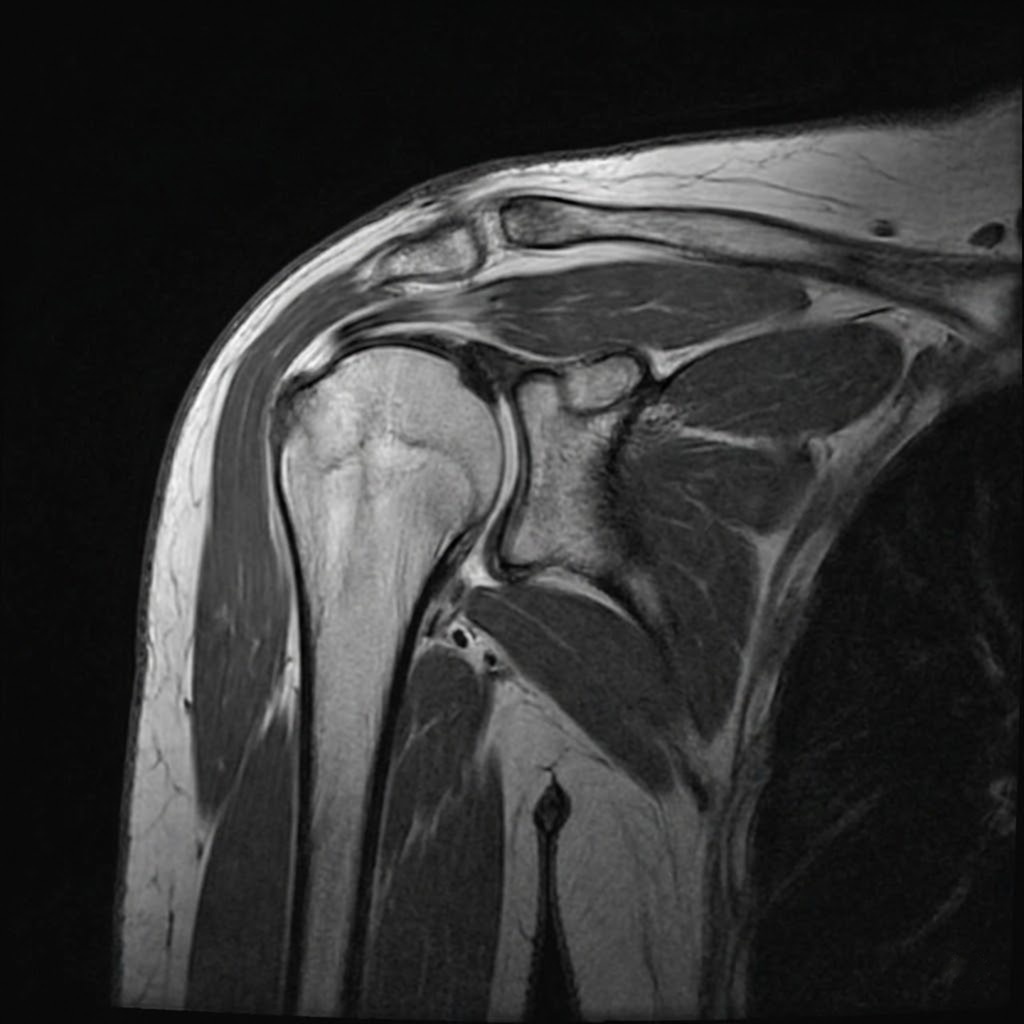

Rotator Cuff Disorders

Comprehensive management of rotator cuff tears and tendinopathy

Diagnostic Assessment

Comprehensive evaluation using advanced imaging and clinical examination to accurately diagnose your condition.